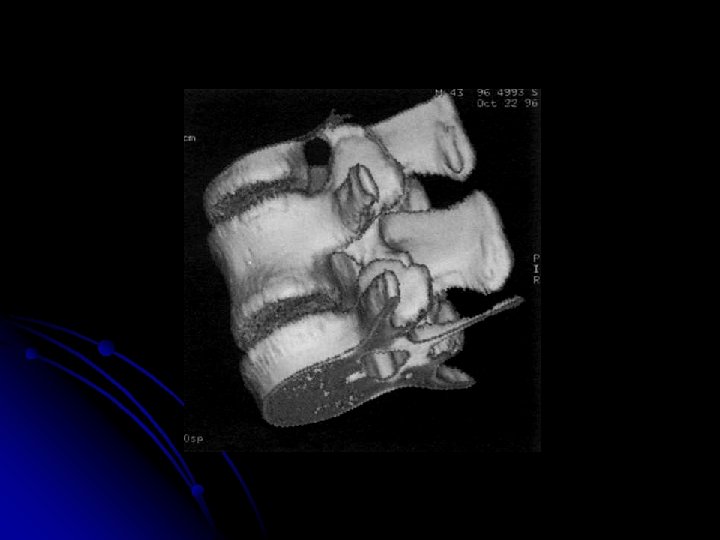

l Particularités selon les indications l Pathologie traumatique l Installation du patient prudente. l Les coupes seront au minimum jointives, voire chevauchées. l Acquisition hélicoïdale avec reconstructions 2 D: ++++, (liberté du canal rachidien) l La technique de superposition d'images permet de comfirmer une éventuelle rotation (dans les luxations rotatoires C 1 -C 2 par exemple). l Pathologie tumorale l Coupes jointives ; l Injection de produit de contraste +++